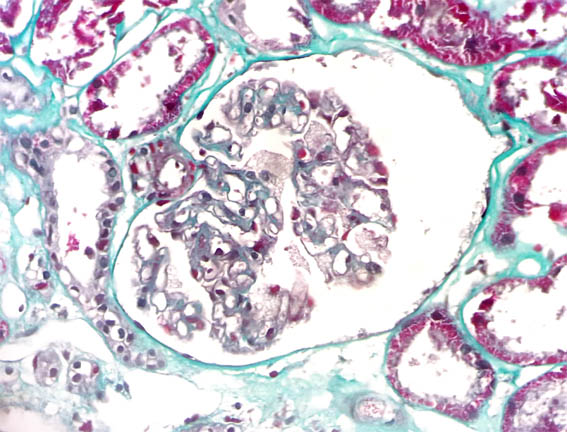

Clinical information

See the images of the renal biopsy.

Figure 3. PAS, X400.